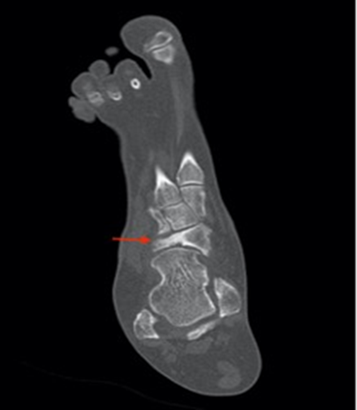

Ct scan is

also useful for diagnosis and plays an important role in the preoperative

assessment by evaluating the bone’s structure and their mineralization (figures 3,4).

Figure 4. Coronal ct scan illustrating the collapse of the

lateral part of the navicular bone (red arrow) associated with medial

subluxation.